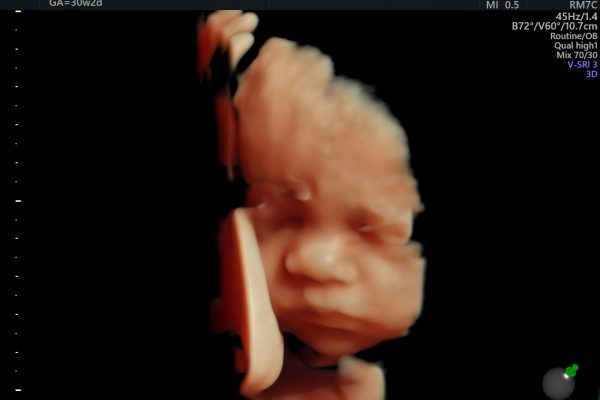

Medico je danas specijalna bolnica s integriranom kompletnom dijagnostikom, poliklinikom i minimalno invazivnom kirurgijom. Naš iskusan i educiran medicinski kadar brine o pacijentima u devetnaest registriranih djelatnosti koje obavljamo kroz mnogobrojne specijalnosti i subspecijalnosti: medicinsko – biokemijski laboratorij, citologija, radiologija, interna medicina, gastroenterologija, kardiologija, nefrologija, pulmologija, hematologija, endokrinologija, neurologija, dermatologija i venerologija, oftalmologija, otorinolaringologija, urologija, ginekologija i opstetricija, opća kirurgija, neurokirurgija, ortopedija, vaskularna kirurgija, plastična kirurgija, anesteziologija, reanimatologija i intenzivno liječenje, reumatologija i psihijatrija.